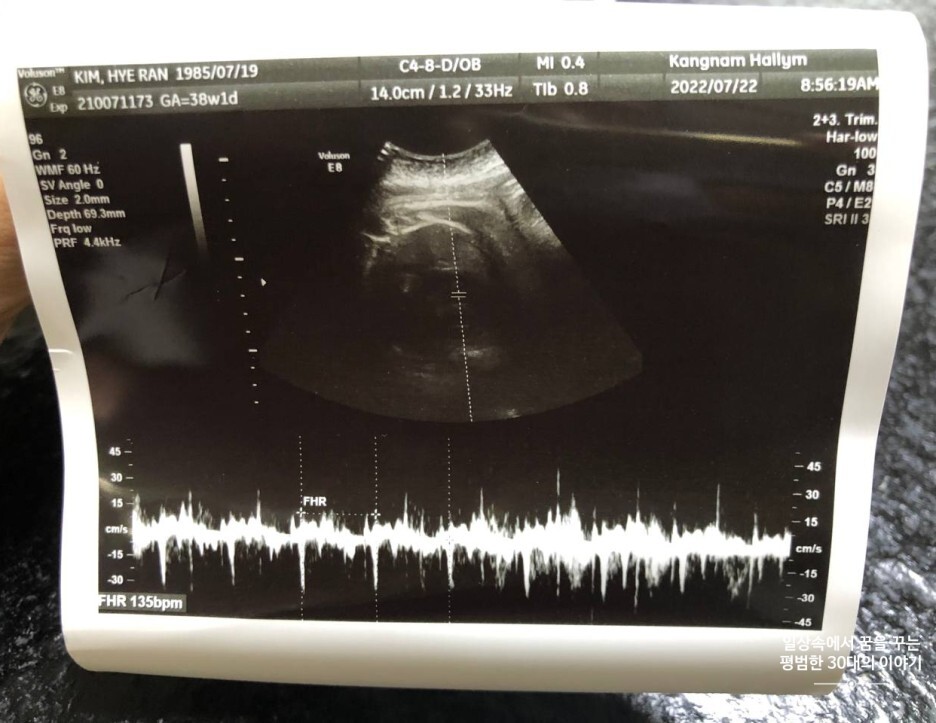

7월 22일 금요일(38주 차 1일)

GA(Gestational Age, 임신 주차): 38주 차 1일

FHR(Fetal Heart Rate, 심장박동 수): 135bpm

일주일 만에 다시 찾은 병원. 37주 차 이후부터는 일주일에 한 번씩 정기검진을 받으러 간다. 다행히 지난주에 받은 막달 검사 결과에는 특이한 이상 소견은 없었다. 오늘은 태동 검사, 초음파검사 그리고 첫 내진을 했다. 태동 검사 상 이안이는 뱃속에서 너무나 잘 놀고 있었고 수축은 전혀 잡히지 않았다.(이안이가 뱃속에서 너무 잘 놀아줘서 10분 만에 검사 끝남) 문제는 이안이의 몸무게인데 지난주보다 320g 정도 늘어서 거의 3.7kg에 육박한다는 것이었다. 나는 처음부터 자연분만을 원했는데 의사선생님 소견에 따르면 이 추세라면 40주 차에는 4kg이 넘어 자연분만이 어려울 수 있다는 것이다. 내진 결과 속 골반이 좁은 건 아니지만 38주 차인 지금, 자궁문도 하나도 안 열린 데다가 이안이도 밑으로 하나도 내려오지 않아서 유도 분만을 한다 해도 결국엔 제왕절개로 출산해야 할 가능성이 높다고 하셨다.(참고로 다들 내진이 아프다고 하던데 나는 전혀 안 아팠고 시험관 배아 이식할 때랑 비슷한 느낌이었다) 물론 의사선생님 말로는 이렇게 자궁문도 하나도 안 열리고 아기가 밑으로 하나도 내려오지 않은 경우라도 갑자기 자연 진통이 올 수 있으니 희망을 버리지 말라고 하셨긴 하지만 아기가 너무 큰 지금 고민이 많다. 제왕절개는 한 번도 생각해 보지 않은 옵션인지라;;; 우선 다음 주 39주 차 진료 때, 아기 몸무게를 다시 한번 체크하고 유도 분만을 할지 제왕절개를 할지 정하자고 하셨다. 다음 주까지 이안이가 너무 크지 말아야 할 텐데 막달이라 그런지 쑥쑥 자라는 상황이라 마음의 준비를 여러모로 해야 할 듯하다.